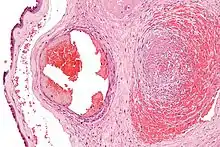

Micrograph showing fibrin (dark pink amorphous material) in a blocked vein surrounded by extravasated red blood cells (right of image). An artery (left of image) and the amnion (far left of image) is also seen. Placenta in a case of fetal thrombotic vasculopathy. H&E stain.

Excessive generation of fibrin due to activation of the coagulation cascade leads to thrombosis, the blockage of a vessel by an agglutination of red blood cells, platelets, polymerized fibrin and other components. Ineffective generation or premature lysis of fibrin increases the likelihood of a hemorrhage.